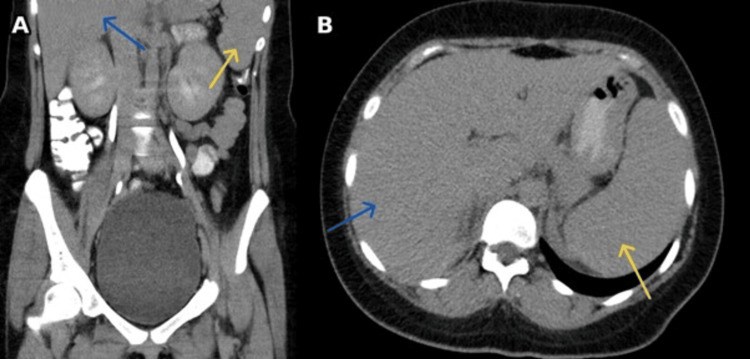

Adult-onset Still's disease (AOSD) is a rare autoinflammatory disorder typified by quotidian fevers, an evanescent salmon-colored rash, arthralgia, neutrophilic leukocytosis, and markedly elevated inflammatory markers. Diagnosis is clinical and by exclusion, supported by classification frameworks like the Yamaguchi criteria. A previously healthy lady in her 20s presented with fever above 39°C, severe generalized myalgia, pharyngitis, a transient salmon-colored rash, neutrophilic leukocytosis, and markedly elevated inflammatory markers. Competing infectious, autoimmune, and malignant etiologies were excluded. Based on clinical features and Yamaguchi criteria, AOSD was suspected. She improved rapidly with intravenous methylprednisolone pulse therapy. During steroid taper as an outpatient, she developed a biochemical flare with ferritin rising to 8,807 ng/ml; tocilizumab was initiated for disease control. This case underscores prompt recognition of AOSD after exclusion of mimics, the interpretive value of ferritin trends, and successful escalation to interleukin-6 (IL-6) blockade for relapse, consistent with emerging data emphasizing targeted cytokine inhibition.